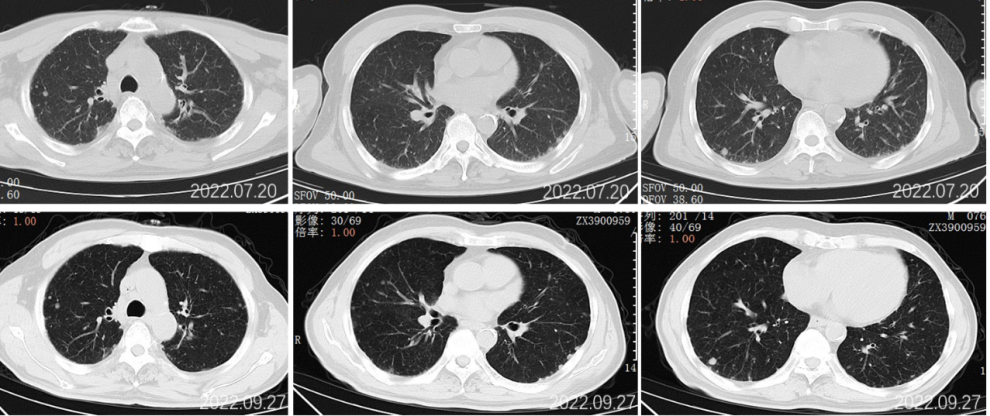

2022.09.27腹部CT增强:肝胆管细胞癌治疗后复查:1、肝右叶多发占位,较前大小相仿,目前仍可见活性;2、肝内及双肾多发小囊肿,相仿;肝S2段小血管瘤考虑,相仿;3、慢性胆囊炎改变;4、肝内钙化灶;前列腺钙化灶。

2022.11.25腹部CT增强:肝胆管细胞癌治疗后复查:对比2022-09-27日:1、肝右叶多发占位,较前大小相仿,目前仍可见活性;2、肝内及双肾多发小囊肿,相仿;肝S2段小血管瘤考虑,相仿;3、慢性胆囊炎改变;4、肝内钙化灶;前列腺钙化灶。

2023.5.28腹部CT增强:肝胆管细胞癌治疗后复查:对比2022-11-25日:1、肝右叶多发占位,较前相仿;2、肝内及双肾多发小囊肿,肝S2小血管瘤,大致相仿;3、慢性胆囊炎改变;胆囊内点状结石未见显示;4、肝内钙化灶;前列腺钙化灶。

2023.09.29腹部增强CT:肝胆管细胞癌治疗后复查:对比2023-05-28日:1、肝右叶多发占位,较前大致相仿;2、肝内及双肾多发小囊肿,肝S2小血管瘤,大致相仿;3、慢性胆囊炎改变;胆囊周围渗出,较前稍增多;4、肝内钙化灶;前列腺钙化灶;新见盆腔少量积液。